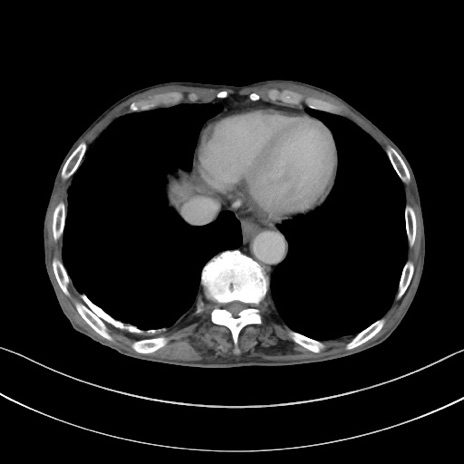

症例3(横断像)

【症例】 70歳代男性

【主訴】右鼠径部腫瘤、疼痛

【現病歴】本日朝より上記主訴あり、受診。

【既往歴】膀胱癌にて膀胱全摘、両側尿管皮膚瘻

【データ】WBC 5600、CRP 0.56